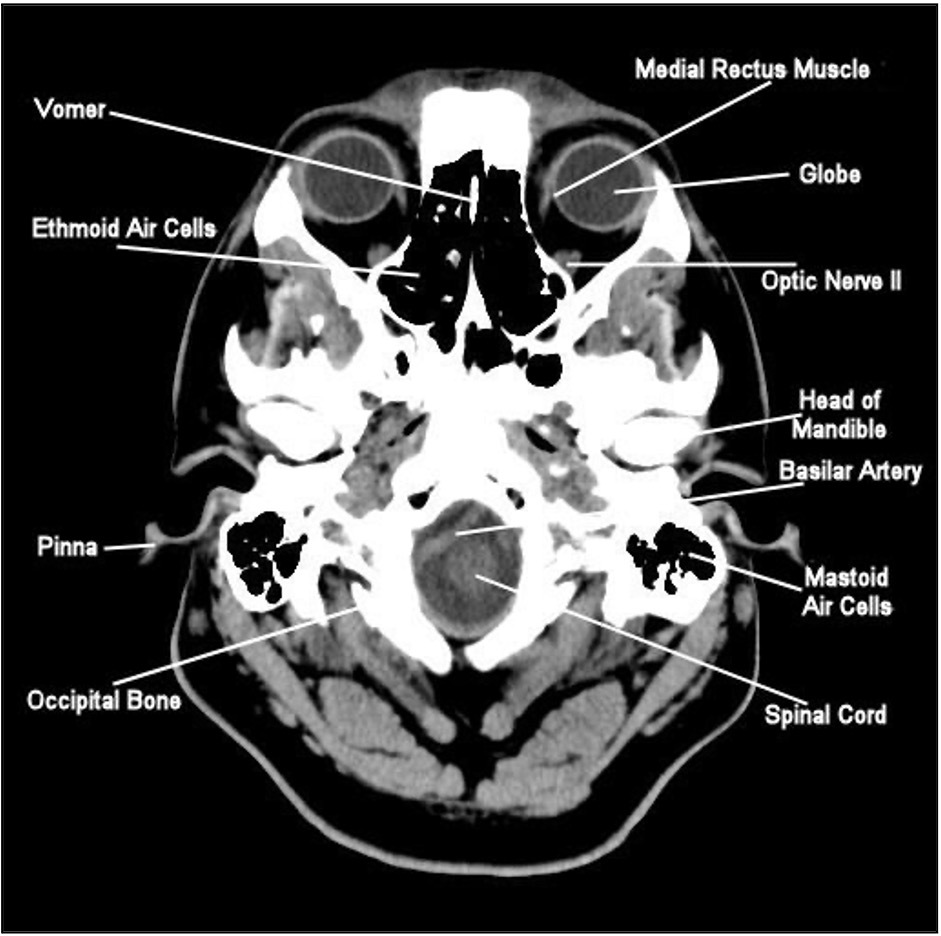

Base of skull

A lot of white, because we see a lot of bone

Note the nasal cavities (black because of air)

The globes, optic nerve, pinna of the ear

Pinna is a tiny bit of the ear.